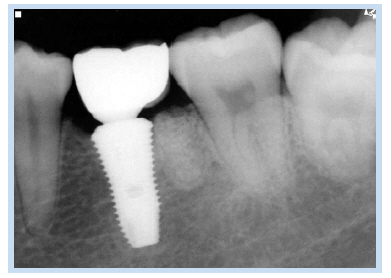

69세 여자 환자가 하악 좌측 제1, 2대구치 상실로 인한 저작의 어려움을 주소로 내원하였다. 하악 좌측 제1, 2대 구치는 6년 전 발치된 상태였고, 하악 좌측 제1대구치의 치근이 잔존해 있는 상태였다(Fig. 1). 내원하기 1개월 전 하악 좌측 제1대구치 부위에 통증이 있었다고 하였지만, 내원 시에는 통증이 없는 상태였다. 심장센터에서 부정맥 치료 중인 환자로 하악 좌측 제1대구치 잔존 치근을 발거하고 하악 좌측 제1, 2대구치 부위에 임플란트를 식립하기로 계획하였다. #46 잔존 치근을 발거하고 치조정 절개를 가하여 피판을 거상한 후 임플란트 drilling을 시행하였다. 그 후 하악 제1대구치에 직경 4.8 mm, 길이 1.5 mm의 임플란트, 하악 제2대구치에 직경 4.8 mm, 길이 10 mm의 임플란트를 일회법으로 식립(Osstem SS II; Osstem Implant, Seoul, Korea)하였다. 치유 지대주(healing abutment)를 연결 후 피판을 재위치시키고 4-0 Vicryl (Johnson & Johnson, New Brunswick, NJ, USA)로 봉합하였다. 임플란트 식립 1주일 후 봉합사를 제거하고 파노라마 방사선 사진과 치근단 방사선 사진을 촬영하였다. 이때 #36 부위에 원심 치근으로 추정되는 방사선 불투과상이 관찰되었으나 감염 등 특별한 증상이 없었고 잔존 치근을 무리하게 제거한다면 그로 인한 골소실 및 임플란트 골유착에 오히려 방해가 될 수 있다고 판단하여 잔존시킨 상태에서 정기적 관찰을 결정하였다(Fig. 2, 3). 임플란트 식립 2개월 후 최종 보철물이 장착되었으며 임플란트 식립 후 115개월간의 치근단 방사선 사진을 통한 경과 관찰 시 안정적으로 임플란트가 유지되고 있음을 관찰할 수 있었다(Fig. 4, 5).

Fig. 4. Follow-up periapical radiograph. (A) Periapical radiograph 4 months after implant placement. (B) Periapical radiograph 12 months after implant placement. (C) Periapical radiograph 67 months after implant placement. (D) Periapical radiograph 87 months after implant placement.

Jun-Bae Sohn et al. : Implant Placed in Contact with Retained Root: Case Reports. Implantology 2016